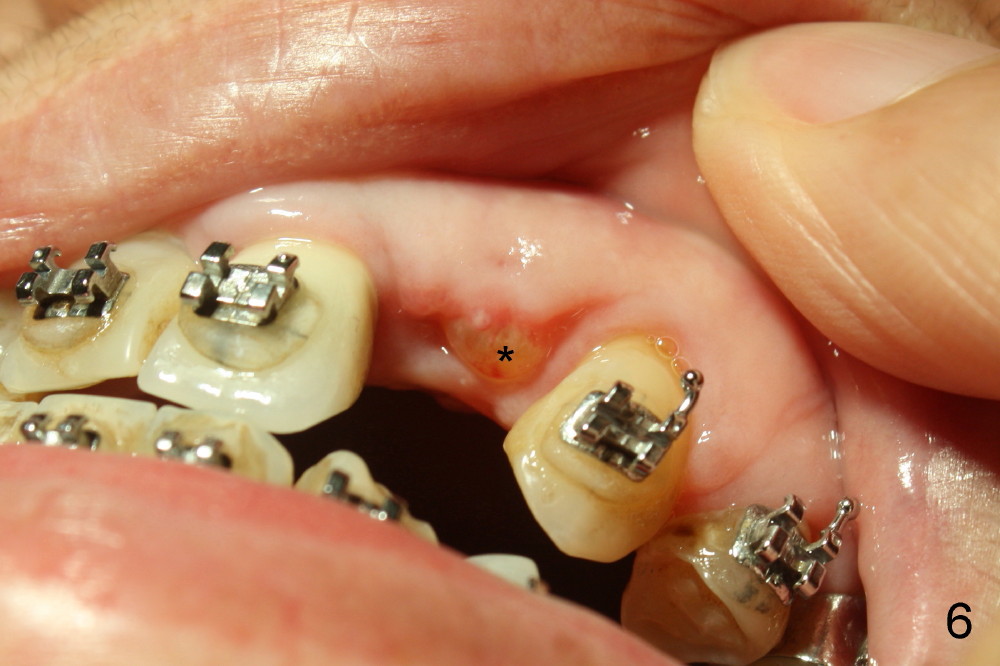

A prominent feature of implant failure in this case is pain. The patient feels that the pain is from the base of the nose. PA taken 3 days postop shows that the implant is inferior to the nasal floor (Fig.2 red ^). Clinically, the buccal gingiva continues to be erythematous 10 days postop (Fig.1). The pain is so unbearable that the implant (3.8x14 mm) is removed 10 days post placement. After repeated debridement, a 4.1 mm tap (Fig.3 T) is manually inserted with torque. A 4.1x14 mm submerged implant is placed with insertion torque < 30 Ncm, but it is placed subcrestally (Fig.4 <--). This time an immediate provisional is not provided. The flap is sutured. The pain disappears immediately. No infection is found 7 days postop (Fig.5). However, an asymptomatic vesicle is noted at the crest 3 weeks postop (Fig.6). The gingiva looks normal 2 and 3 months postop (Fig.7,8). The coronal gap dissolves 3 months postop (Fig.9 >, as compared to Fig.4), suggesting osteointegration. The implant is uncovered 4 months postop (Fig.10). Bracket is placed 5 months postop (Fig.10'). One month later, the left central incisor improves in position coronocervically (Fig.11), but the overjet needs correction by distalization of the upper anterior teeth. The implant at the site of #10 may be used as an anchorage.